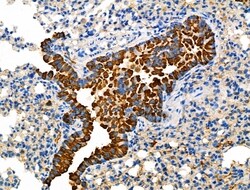

Invitrogen™ Glypican 3 Polyclonal Antibody

Antibody detects endogenous levels of total GPC3.

| Applications | Immunohistochemistry (Paraffin), Western Blot, Immunocytochemistry, Western Blot |